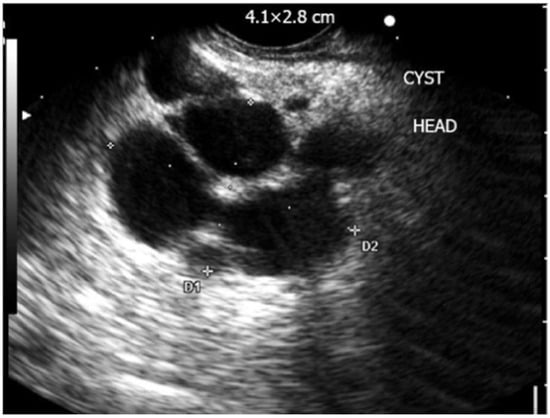

| Pancreatic Pseudocyst [37,38,39] | Anechoic, well-circumscribed, round or oval lesion, absence of septations and mural nodules | Low | High |

| Intraductal Papillary Mucinous Neoplasm [38,40] | Macrocystic-type lesion with occasional parenchymal changes and communication with pancreatic duct | High | High |

| Serous Cystadenoma [38,40] | Multiple microcysts (<3 mm) in a cystic lesion, possible honeycomb-like appearance, no ductal communication | Low | Low |

| Mucinous Cystic Neoplasm [38,41] | Cysts with septations of variable thickness, visible wall with occasional peripheral calcifications, no ductal communication | High | Low |

| Solid Pseudopapillary Neoplasm [38] | Mixed solid-cystic well-demarcated tumor | Low | Low |